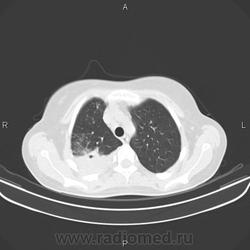

Задействован весь сегмент S2 справа. Полость деструкции. Перисциссурит. Можно сказать, ограничено со всех сторон плеврой. Мелкоочаговие высоко- и среднеинтенсвные тени в S1, S3 и S6 - отсев. Симптом позитивной воздушной бронхограммы. Объективных данных мало, но это инфильтративный туберкулёз сегмента S2 правого легкого в фазе распада и дессименации.

Спасибо всем ещё раз. Описывая КТ нашел ещё отсев в S1,3,6,10 правого легкого и S3,6 левого легкого. Так что туб этиология вызывает все меньше сомнений.

Больше данных за инфильтративный туберкулёз с распадом и обсеменением, но всё-таки абссцедирующую пневмонию из диф.ряда я бы не убирал, т.к. ни в одном из очагов не вижу признаков пресловутого казеоза( вкраплений извести).Было бы хорошо, если бы вы предствили R-граммы 2-недельной давности, кстати отсутствие по ним динамики, на фоне антибактериального лечения ещё не доказывает туберкулёзный процесс, т.к. есть пневмонии с затяжным течением и может быть прогрессирование пневмонии на фоне лечения. Необходима консультация фтизиатра.

уплотнение в верхней доле с распадом, односторонними ценрилобулярными узелками,без поражения левого легкого-сомнительно сразу писать tbc,включить бронхиолит,атипичную пневмонию,грибковое поражение (аспергиллез) в д.д ряд